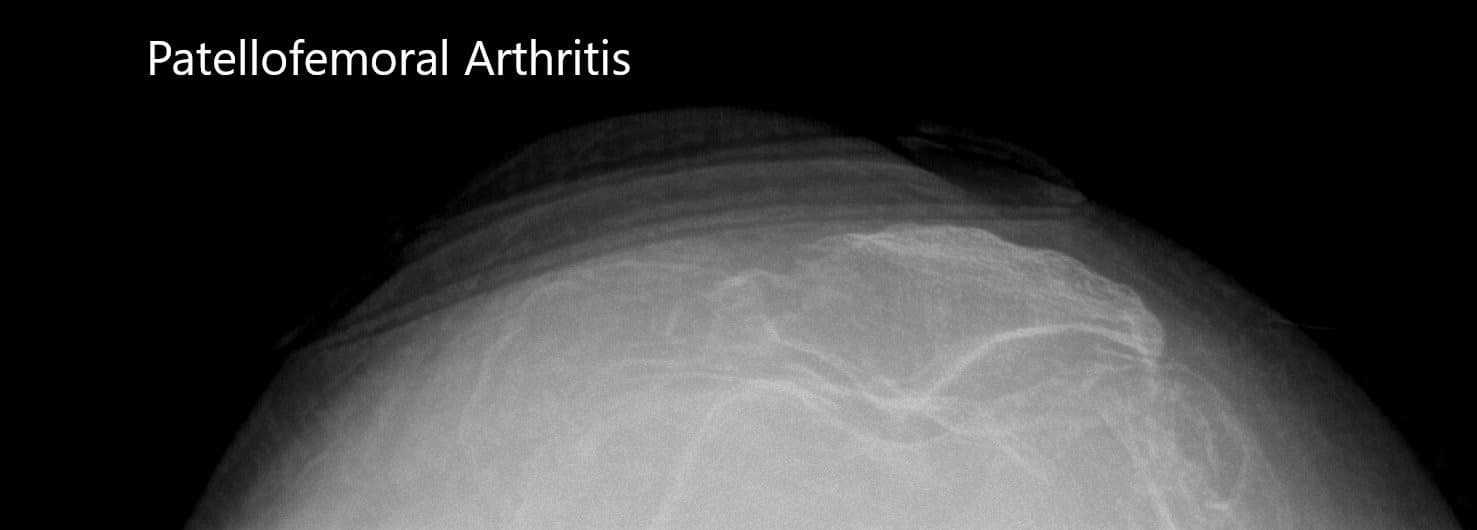

Vistas comerciales preoperatorias de la rótula bilateral que muestran osteoartritis severa del compartimiento patelofemoral.